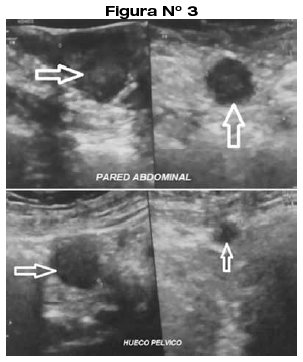

La química sanguínea básica se encontraba dentro de parámetros normales, las pruebas para HIV, hepatitis y RPR eran no reactivas. La Placa de Rayos X de tórax y abdomen no reportaron hallazgos. Se realizó Ecografía de rastreo abdominal y de hueco pélvico, evidenciando lesiones nodulares en pared abdominal, y en hueco pélvico a predominio izquierdo (Fig 3), por lo que se realiza Tomografía Computarizada, evidenciándose múltiples metástasis en hueco pélvico, hígado, estomago, pulmón y cerebro.